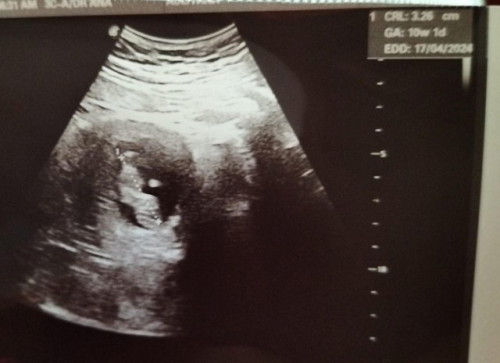

ALHAMDULILLAH BABY MEMBESAR DENGAN SIHAT

Alhamdulillah w semalam g klinik swasta semata2 nak g scan baby (2nd appt di KK 3/10 lambat lagi 😆), first to be mom setelah 7tahun menanti mmg excited sgt2. Syukur scan baby dah pusing2 golek2 dlm perut mummy, besar mengikut tarikhnya, dengar heartbeat so cute. Semoga Allah jaga kandungan ini dan membesar dgn sempurna ye anakku. So excited ... alhamdulillah Syukur 🤲 #firstmom #firstbaby